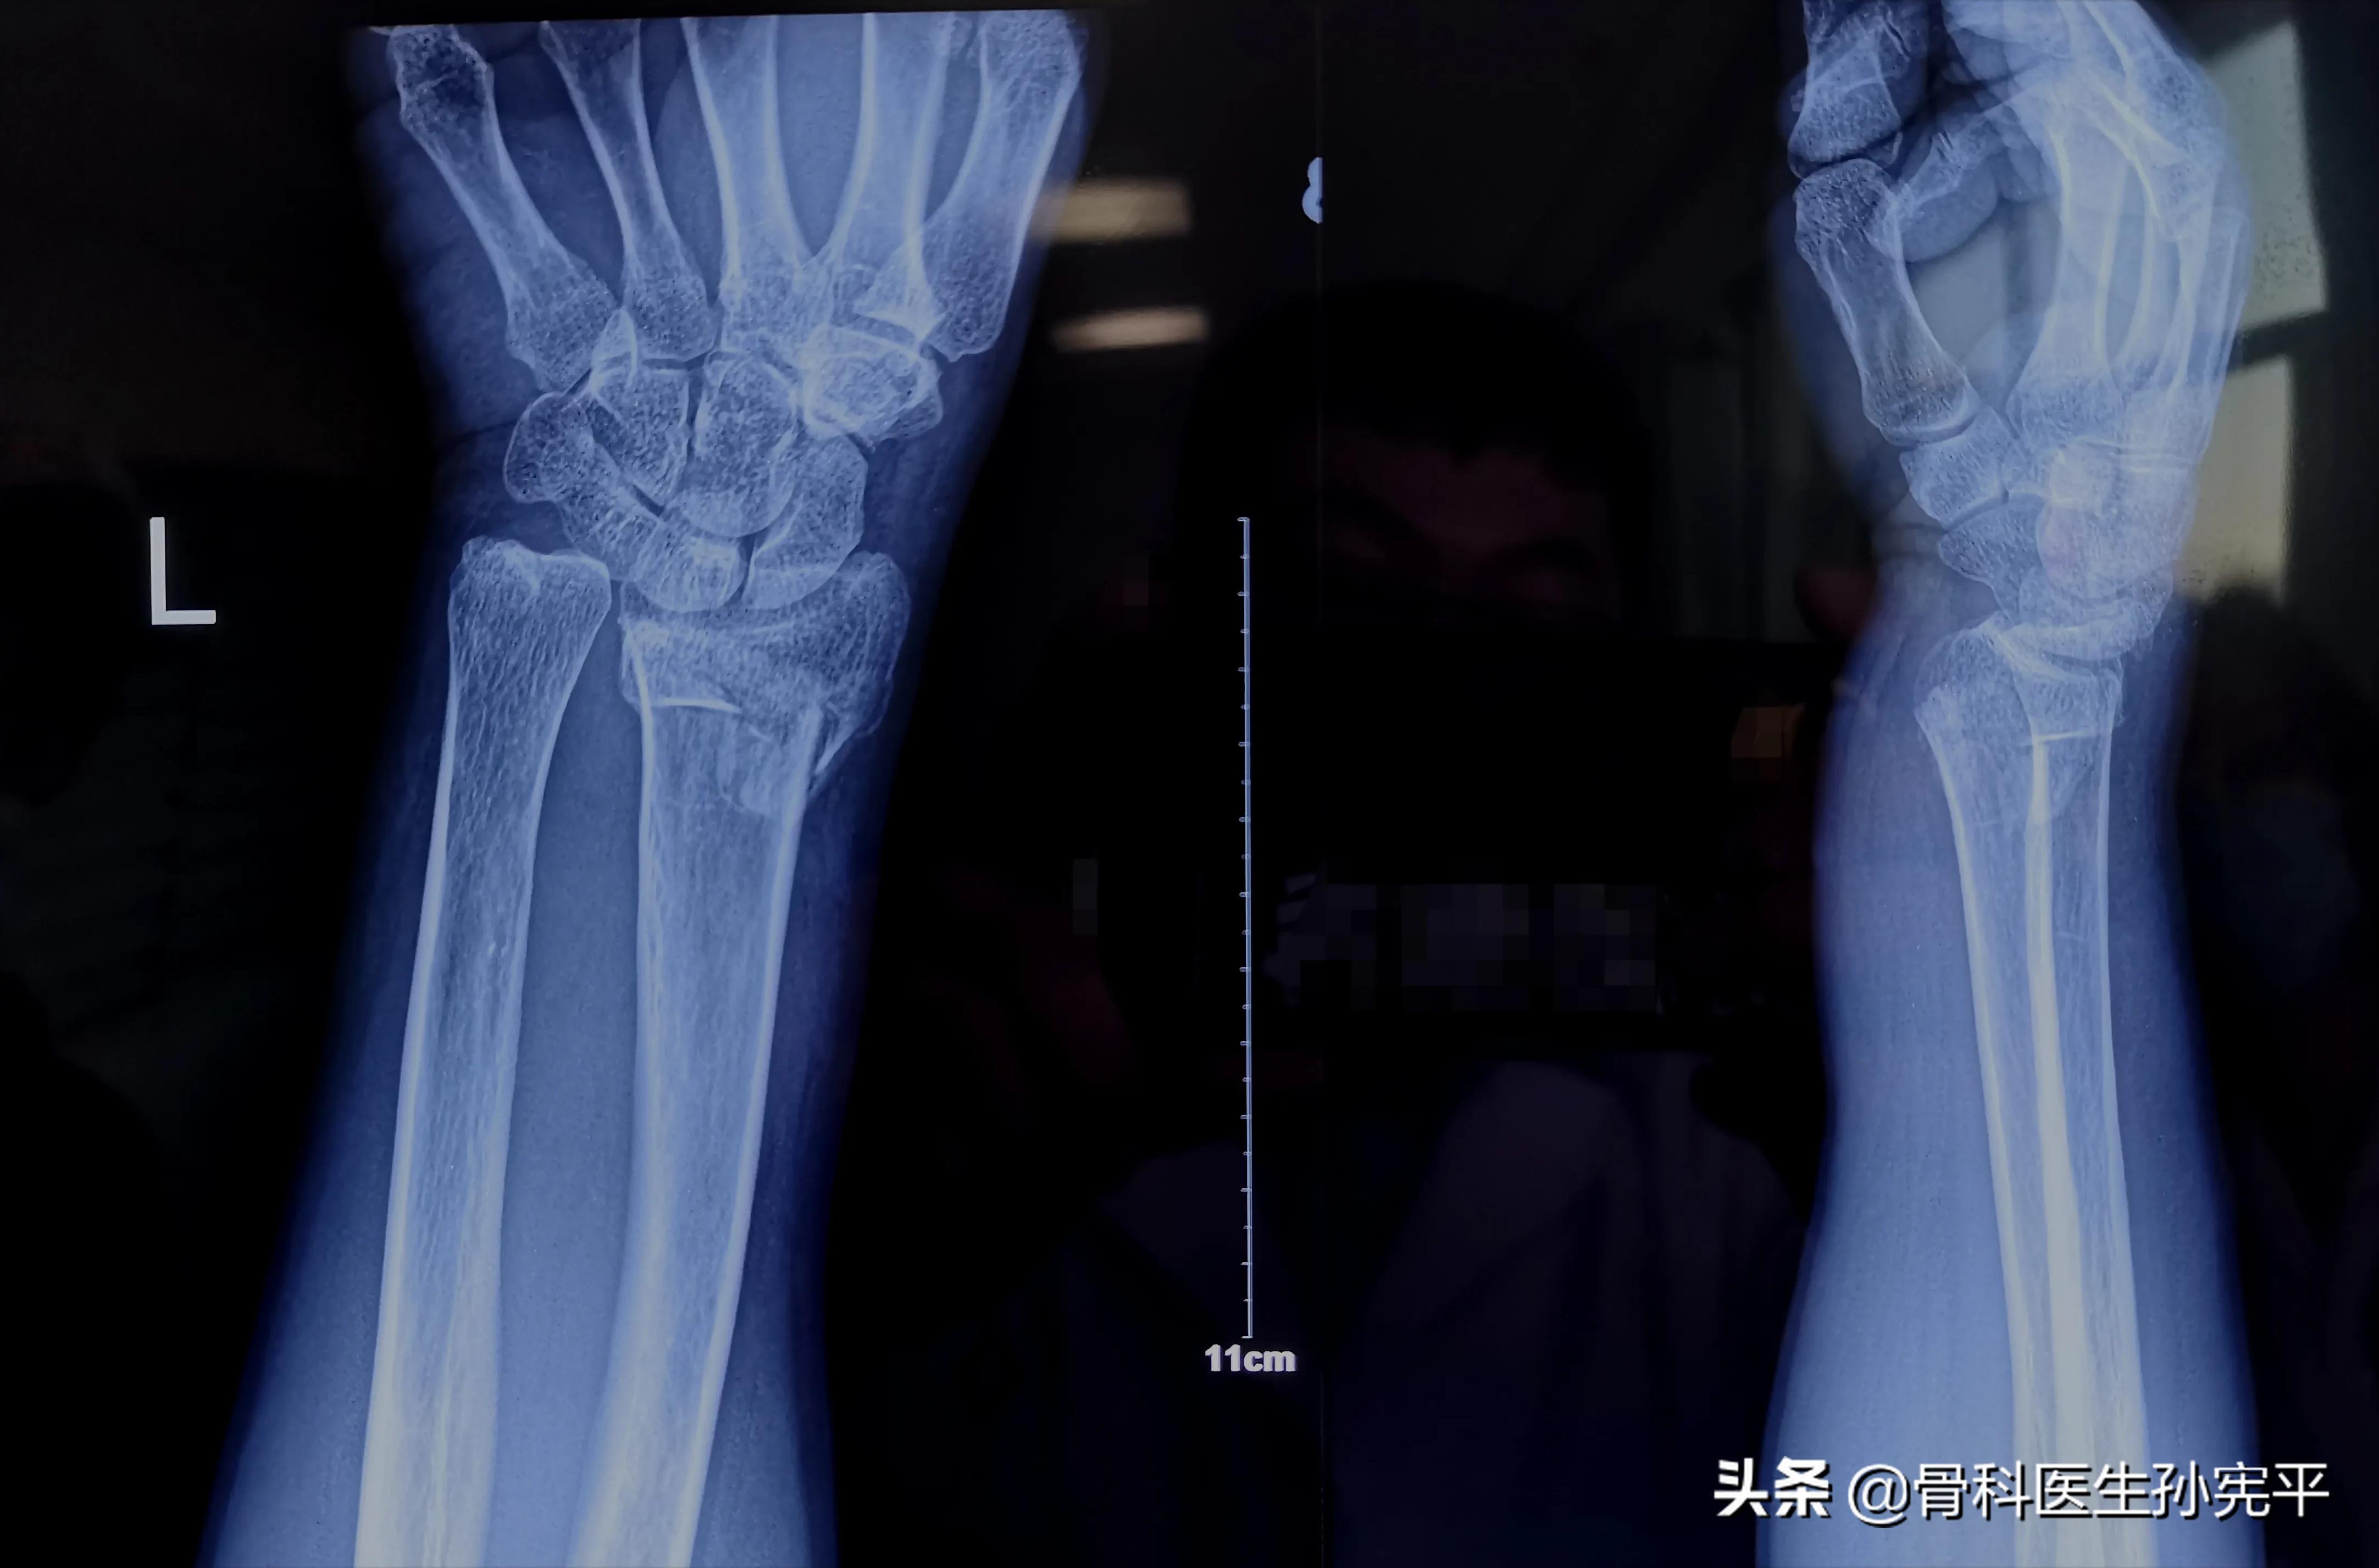

这是一位80多岁的老人,3年前因外伤导致腕部骨折,采取了外敷中药等保守治疗,没有进行有效的骨折复位,结果出现了骨折的畸形愈合,遗留腕关节活动时疼痛、部分受限、手部握力下降等症状。

- 桡骨远端骨折典型的体征“ 银叉”畸形、“枪*刀刺**”畸形 。

对于可疑桡骨远端骨折的病人,首选的辅助检查为腕关节X线片。对于骨折碎裂移位严重的病人,尤其是累及关节面的骨折,可以进一步行腕关节CT检查,从而更好的明确关节面塌缩碎裂移位情况,从而为优化治疗方案提供有力保障。